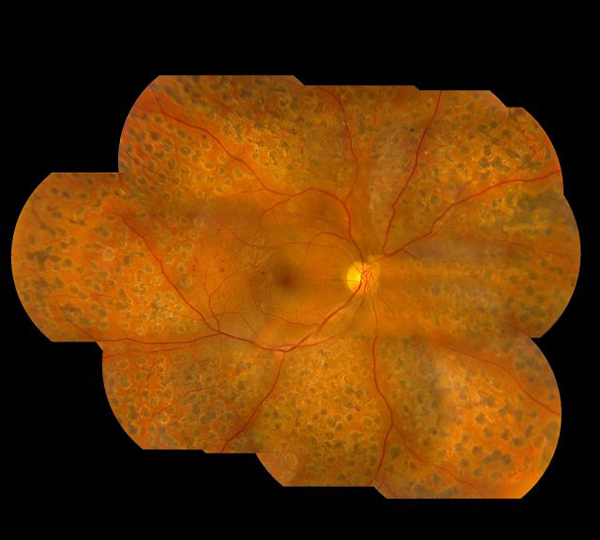

珠海希瑪眼科醫(yī)院:糖尿病視網(wǎng)膜病變,怎么辦?

糖尿病患者視網(wǎng)膜病變?cè)谔悄虿』颊咧惺值膹V泛,患病率十分的高,而且會(huì)伴隨著現(xiàn)病史的增加而迅速提升。糖齡超出三年的,發(fā)病率大概在5%;糖齡超出5年的已達(dá)25%;超出十年糖齡的,發(fā)病率會(huì)超出60%,20年糖齡的則會(huì)達(dá)到90%之上,可以說(shuō)要是糖友活的充足長(zhǎng),基本上每個(gè)人都出現(xiàn)或輕或重的視網(wǎng)膜病變。

此外,糖尿病患者視網(wǎng)膜病變它還是一個(gè)失明率十分高的病癥。研究表明,其失明率是平常人的25倍,是導(dǎo)致在我國(guó)成年人失明的關(guān)鍵緣故,因此 許多 糖尿病患者后都因這一病,而造成 眼睛視力大損,乃至徹底失明,為自己的后半輩子產(chǎn)生巨大的痛楚和穩(wěn)定隱患。

簡(jiǎn)易地說(shuō),糖尿病患者視網(wǎng)膜病變便是因?yàn)樘悄虿』颊哐侵甸L(zhǎng)期性操縱不太好,造成 全身上下各機(jī)構(gòu)人體器官的毛細(xì)血管發(fā)生了變病。毛細(xì)管周邊的細(xì)胞凋亡,從而造成 內(nèi)皮細(xì)胞變軟變脆、內(nèi)天然屏障作用損傷,以致于毛細(xì)血管內(nèi)的液體成份由毛細(xì)血管內(nèi)滲進(jìn)機(jī)構(gòu)中,乃至裂開(kāi)流血,或是新生兒毛細(xì)血管產(chǎn)生,進(jìn)而導(dǎo)致視網(wǎng)膜病變和功能問(wèn)題。

視網(wǎng)膜病變依據(jù)變病的特性和水平,臨床醫(yī)學(xué)上把它分成兩種類型六期,前三期為單純性型視網(wǎng)膜病變,又叫情況期或者非繁衍期;后三期則為繁衍型視網(wǎng)膜病變,又叫繁衍期或新生兒毛細(xì)血管期。

假如實(shí)際到臨床表現(xiàn),在查驗(yàn)眼眸時(shí),大家會(huì)發(fā)覺(jué):

1.眼眸具體表現(xiàn)為有微神經(jīng)纖維瘤和血點(diǎn);

2.會(huì)出現(xiàn)強(qiáng)制外滲及流血斑;

3.主要表現(xiàn)為柔性外滲及流血斑;

4.主要表現(xiàn)為眼底黃斑新生兒毛細(xì)血管產(chǎn)生和或玻璃體出血;

5.主要表現(xiàn)為新生兒毛細(xì)血管產(chǎn)生并由此可見(jiàn)化學(xué)纖維繁衍;

6.則在所述基本上出現(xiàn)視網(wǎng)膜剝離。